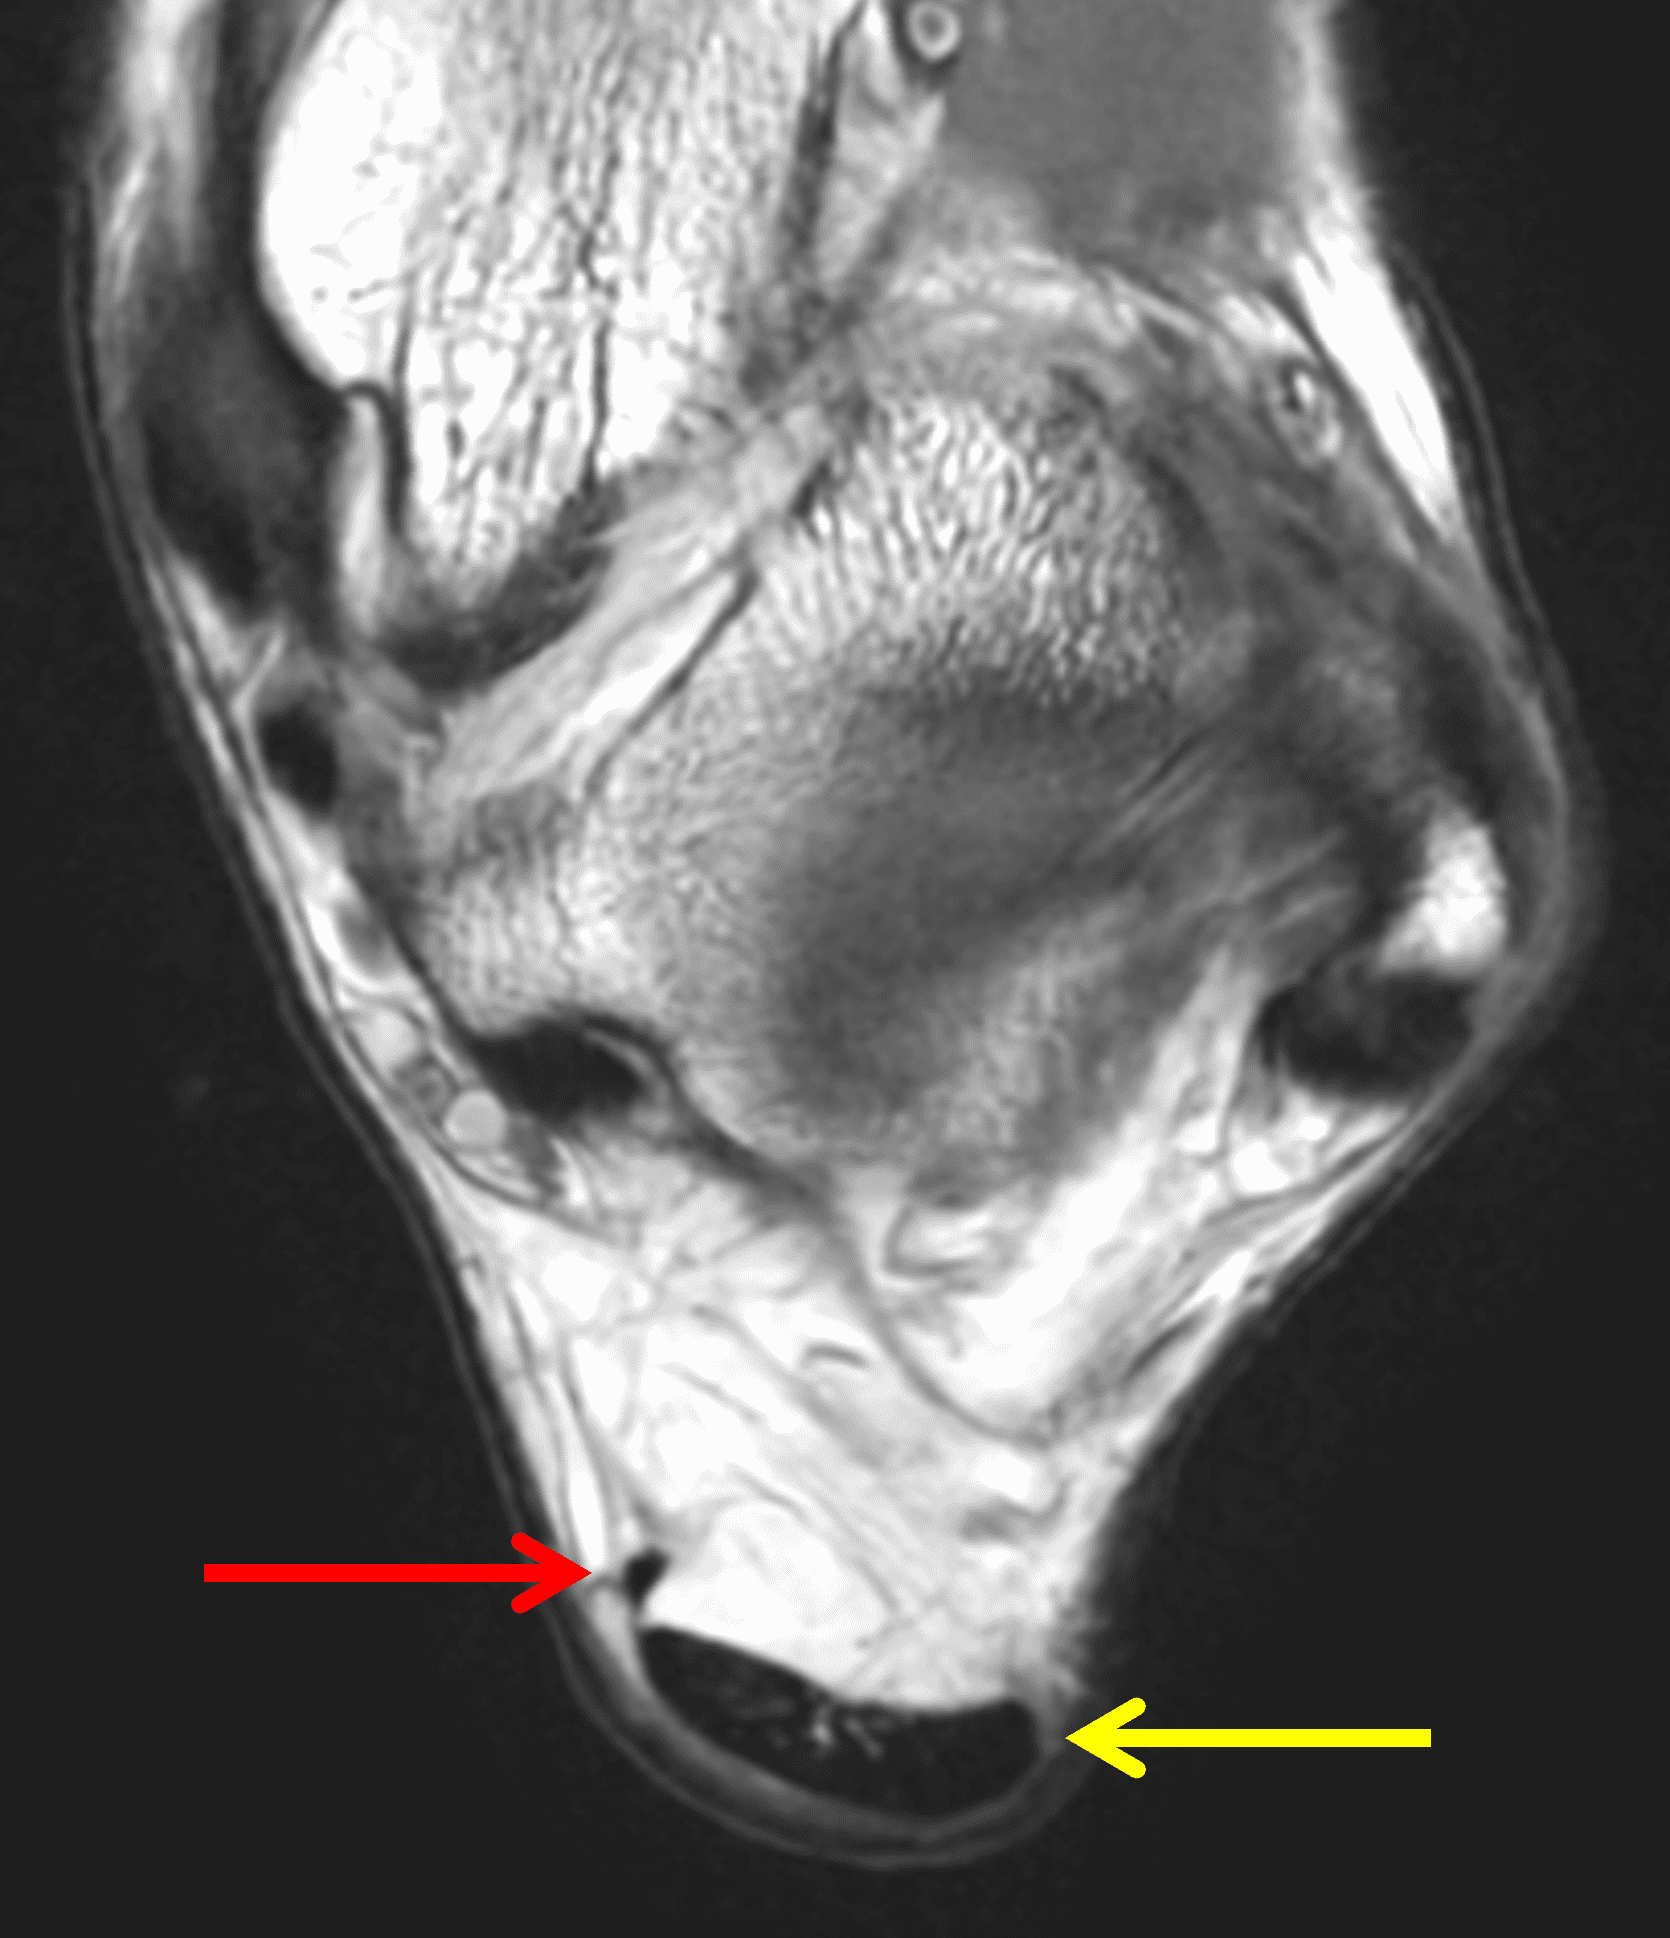

On MR images, the normal Achilles tendon demonstrates low signal intensity on all sequences (Figure 4). On sagittal images, the tendon should be uniform in thickness and have a sharp anterior margin where it abuts Kager’s fat pad. High-resolution images may reveal fine punctate or linear intermediate signal from normal interfascicular septa, especially in the distal tendon, which should not be misinterpreted as tendinosis, particularly when the tendon thickness is normal.6 When the tendon fibers are oriented near to 55° with respect to the B0 magnetic field, increased signal may be seen on short-TE sequences due to the magic angle effect, with decreasing artifact on longer-TE sequences. MR images obtained at higher field strengths (3-7 T) accentuate the fascicular detail and normal septations as well as magic-angle effects.5,6 On transverse images, the posterior tendon margin is typically convex; the anterior margin is flat-to-concave along most of its length but may be focally convex at the gastrocnemius–soleus convergence, which is considered a normal variant. The average tendon thickness is approximately 6 mm, with variation by body size, age, and sex.20

The normal Achilles paratenon appears as a thin low-to-intermediate signal rim.6 The retrocalcaneal bursa lies between the distal tendon and calcaneus and normally contains only minimal fluid. The contents of Kager’s fat pad should be isointense to fat on all pulse sequences, with traversing vessels and thin fascial strands that should not be mistaken for pathology.

Figure 4: MRI appearance of the normal Achilles tendon. (4A) Sagittal T1-weighted image shows the low signal intensity Achilles tendon (t) with uniform thickness. Kager’s fat pad (asterisk) normally contains thin fibrous strands and vessels. S = soleus muscle, F = flexor hallucis longus muscle. (4B) Sagittal fat-suppressed fluid-sensitive sequence shows the sharp anterior tendon margin (arrowheads) and a physiologic amount of fluid in the retrocalcaneal bursa (arrow). (4C) Transverse T1-weighted image just proximal to its insertion shows the Achilles tendon (yellow arrow) with a concave anterior margin and convex posterior margin. The much smaller plantaris tendon (red arrow) lies along the anteromedial margin of the Achilles. (4D) Transverse fat-suppressed T2-weighted image shows punctate foci of higher signal intensity (arrowhead) in the distal tendon representing normal interfascicular septa.